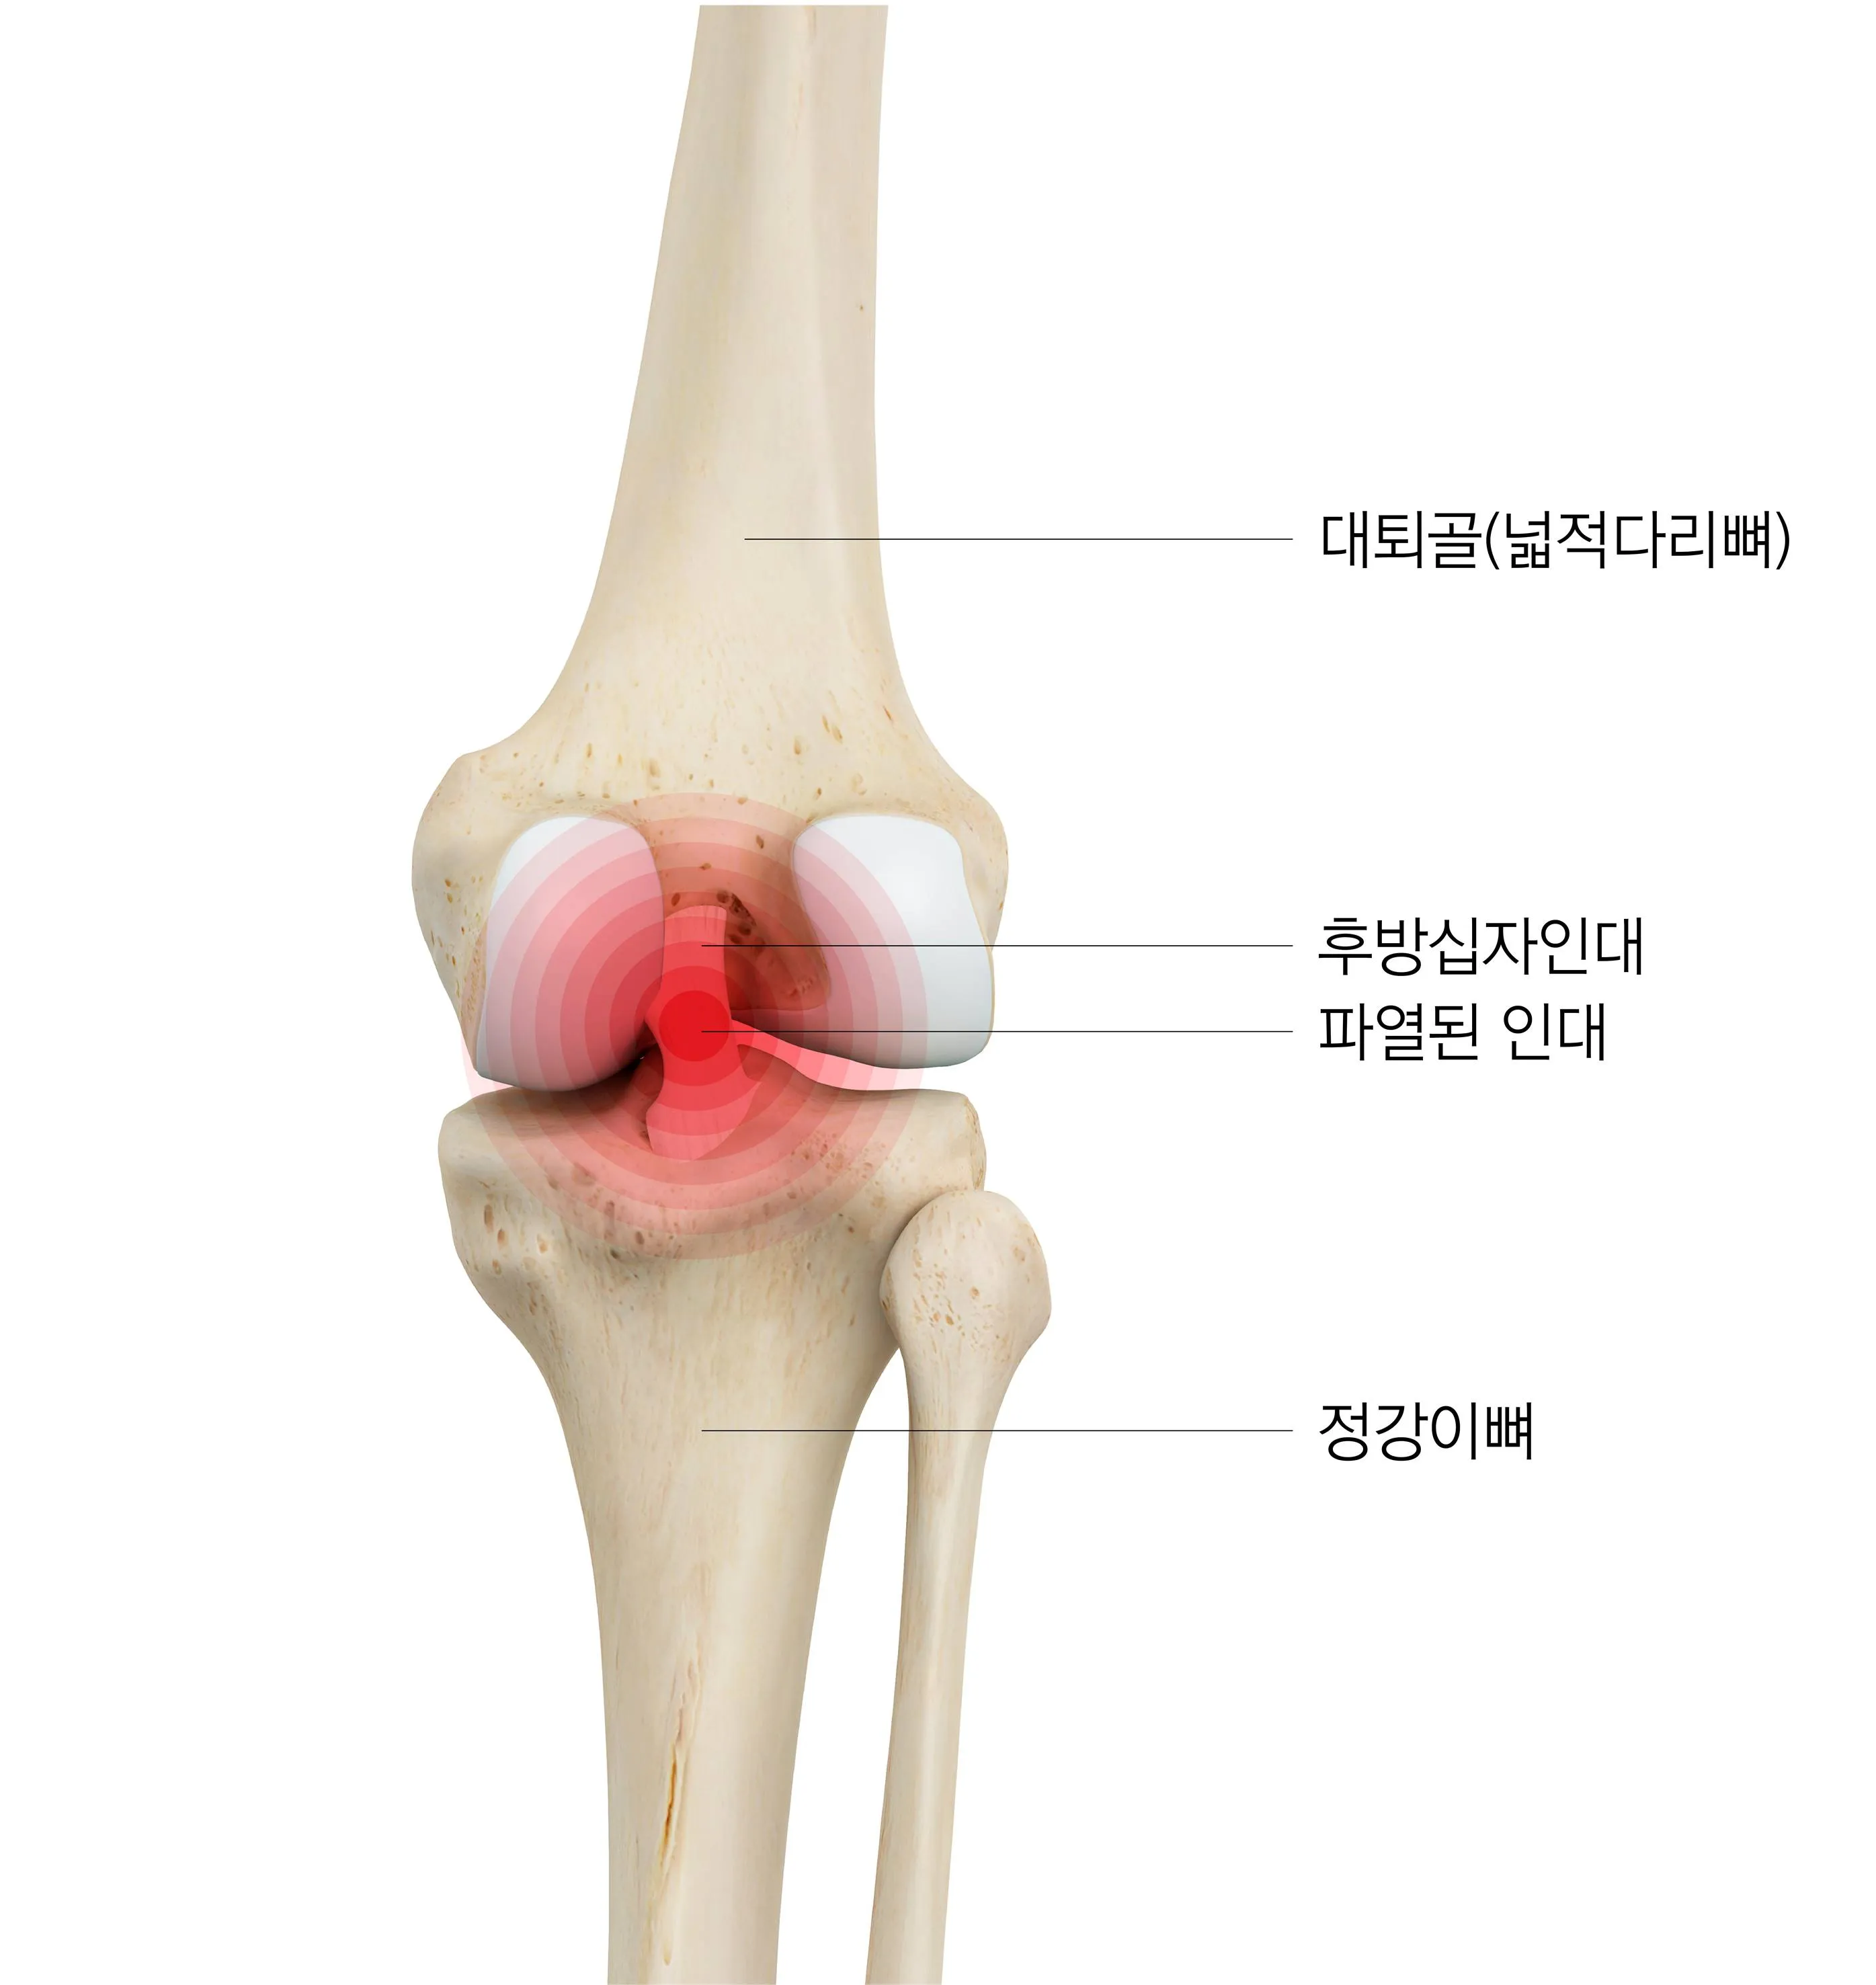

첫 번째는 근육 및 인대의 손상

과도한 사용이나 부상으로 인해 근육이나 인대가 늘어나거나 찢어지는 경우가 있습니다. 이러한 손상은 단순한 통증뿐만 아니라 부기, 멍이 듦, 움직임의 제한 같은 다른 증상들을 동반할 수 있습니다. 이 상황에서의 치료는 대개 휴식, 냉찜질, 압박 붕대 사용, 부위를 높게 유지하는 것과 같은 자가 관리 방법과 필요에 따라 진통제 또는 스테로이드 주사와 같은 의학적 치료로 구성됩니다.